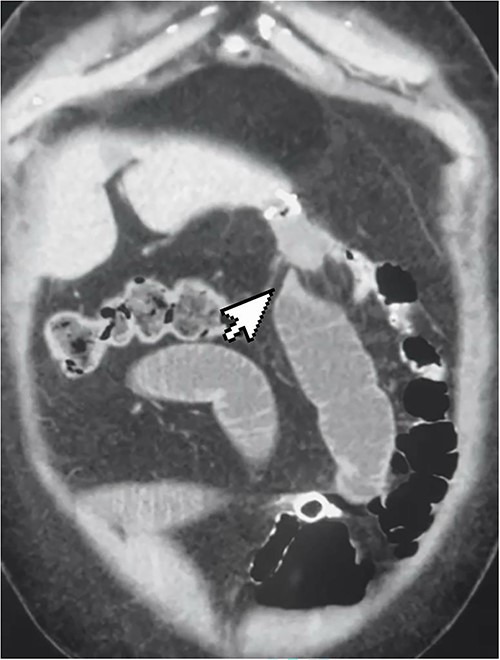

The patient was positioned with split legs. Five laparoscopic ports were used, and insufflation was obtained. Internal herniation was found at the site of the gastro-jejunal anastomosis, showing an apparent mesenteric twist due to adhesions found at Petersen’s space (Fig. 2). Adhesiolysis was carried out by extending the space, allowing the bowel limbs to un-twist, and placing them in the appropriate direction. The Petersen’s space was closed, and both limbs were fixed to adjacent structures to prevent future herniation. A methylene blue test was performed to check the integrity of the anastomosis. All the bowel loops were examined for adhesions and proper configuration (Fig. 3).

Restoration of the anatomy, fixation, and closure of Petersen’s space.